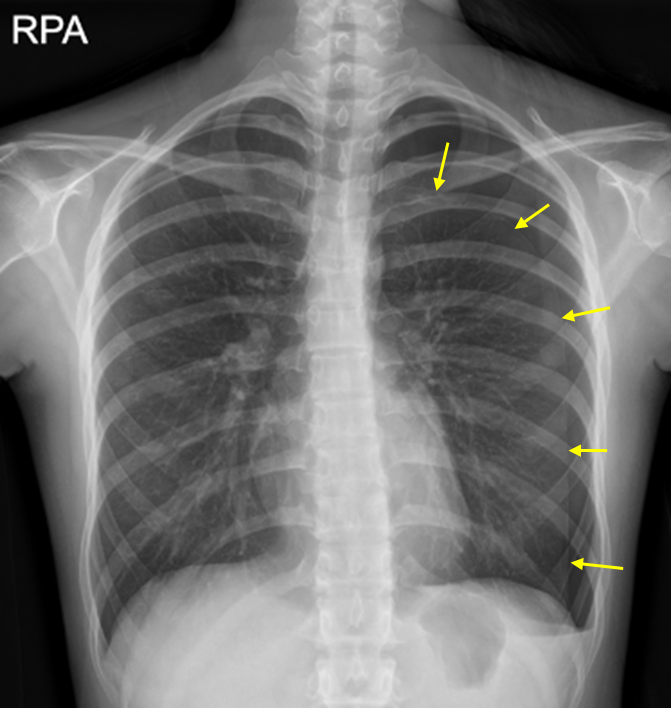

20세 여자가 12시간 전부터 숨쉬기가 답답하다며 병원에 왔다. 마른기침이 있고 기침 시 왼쪽 가슴이 결린다고 한다. 기저질환은 없고, 비흡연자이다. 혈압 119/71 mmHg, 맥박 108회/분, 호흡 20회/분, 체온 36.5℃이다. 가슴 진찰에서 왼쪽 가슴의 호흡음이 감소되어 있고, 타진상 과공명음이다. 가슴 X선사진이다. 진단은?

Img | CXR: Lt. pleural line with loss of vascular markings |

CXR 소견상 기흉으로 진단한다.

• 왼쪽 호흡음의 감소와 동반되는 타진상 과공명음(hyperresonance)은 기흉을 시사한다. CXR에서도 왼쪽 흉부에 pleural line이 관찰되며, 그보다 lateral로는 pulmonary vascular marking이 관찰되지 않으므로 기흉으로 진단할 수 있다.

검사소견 | • CXR: Pleural line 보임, vascular marking이 보이지 않음 |